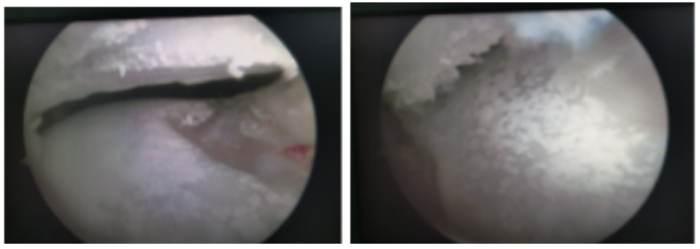

运动医学、关节、骨病科就诊,完善相关检查后,发现他并不是简单的扭伤。后仔细询问病史才发现李先生以前就有尿酸增高的病史,由于一直没有症状,所以就没有引起重视,所以,这次扭伤成了他痛风发作的诱因,目前,李先生已经顺利接受了关节镜术,镜下看到他的软骨上面一层厚厚的“石灰”,经处理伤口恢复良好,关节功能恢复满意。

(关节镜下看到患者的软骨上面一层厚厚的“石灰”)